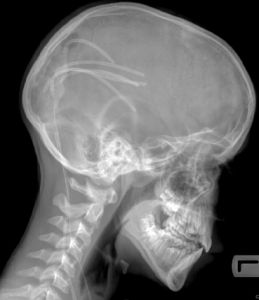

因各種疾病引起的腦室外的腦脊液循環和吸收通路阻塞,進而引起交通性腦積水。病理改變主要表現為腦室系統擴大,腦組織因長期慢性受壓而萎縮變薄,腦回扁平,腦溝變淺。腦萎縮以額葉為著,灰質輕,白質重。兩側腦室多為對稱性擴大,額角和顳角較早受累,且明顯。室管膜可發生斷裂,可在側腦室壁形成憩室或囊腫。常可發生蝶鞍擴大,後床突脫鈣或變薄,基底核及腦幹也可出現萎縮。